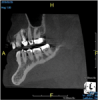

(8.) An original finding of a small lesion on the mesial root of tooth No. 30 was not accompanied by any outward symptoms; therefore, the patient delayed pursuing treatment. When a follow-up CBCT scan was acquired 6 years later, the easy-to-visualize increase in the dimensions of the lesion motivated the patient to elect a treatment plan.

Figure 8

(9.) An original finding of a small lesion on the mesial root of tooth No. 30 was not accompanied by any outward symptoms; therefore, the patient delayed pursuing treatment. When a follow-up CBCT scan was acquired 6 years later, the easy-to-visualize increase in the dimensions of the lesion motivated the patient to elect a treatment plan.

Figure 9

Identifying the shape and location of the roots of teeth to be removed is critical to performing safe exodontia. Some clinicians virtually deconstruct teeth using CBCT images prior to actually sectioning and removing them. Being able to recognize pathoses and differentiate affected structures from normal structures is key in deciding what the treatment should be and when that treatment should be initiated (Figure 8 through Figure 10). The arena of the oral surgeon is larger than that of many general practitioners, involving the sinuses and condyles and other considerations in and around the entire mandible and maxilla. Certain fractures and other conditions that some general practitioners feel uncomfortable treating are often referred for evaluation and treatment by an oral surgeon. Because of this, oral surgeons require the most accurate and complete diagnostic information available. The American Academy of Oral and Maxillofacial Radiology recommends that "cross-sectional imaging be used for the assessment of all dental implant sites" and has stated that "CBCT is the imaging method of choice for gaining this information."18